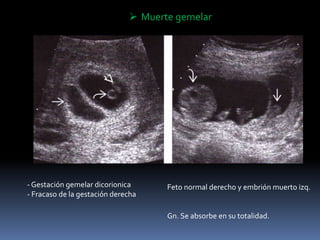

 Muerte gemelar

- Gestación gemelar dicorionica

- Fracaso de la gestación derecha

Feto normal derecho y embrión muerto izq.

Gn. Se absorbe en su totalidad.